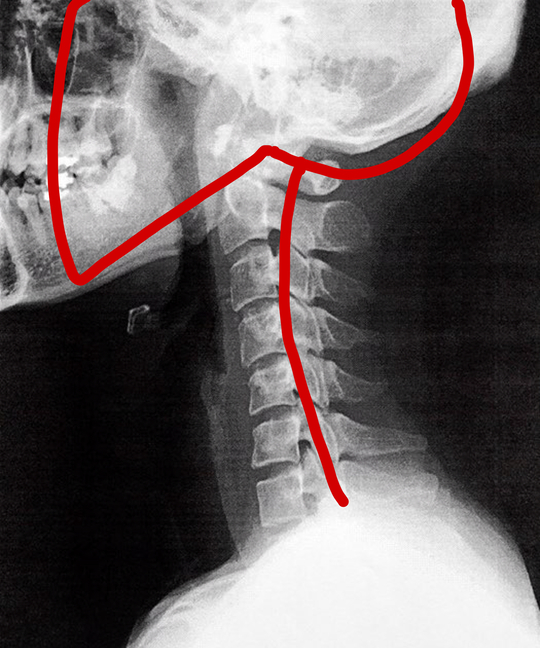

下記の写真のような前弯が頚椎には必要なのです。

ストレートネックの原因についての解説

ストレートネックになると、神経や血管が圧迫され、頭痛や手のしびれなどの症状が出現しやすくなります。

また、肩こりや首こりの原因にもなります。